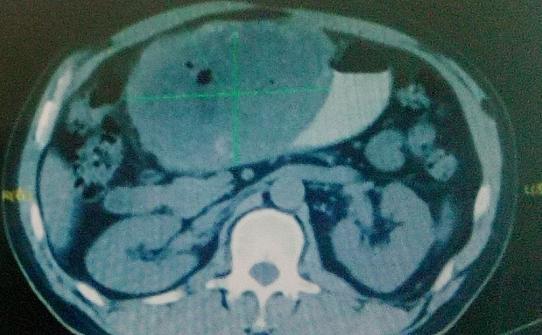

患者于2015年1月2首次入我院。入院时进食稍差,有呕吐,乏力症状,大小便未见异常,体重较前下降约15kg。腹部超声提示:肝左叶体积明显增大,形态失常,可探及多发稍高回声团块,较大者呈“巨块型”,长径30cm,明显外凸,占据整个中部腹腔,边界不清,形态不规则。

完善各项入院检查后,行缓释库治疗多次,于2015年10月1日复查腹部CT:肝左叶巨大肿块,肝肿瘤明显缩小,最大截面约13.5cmx 11.1cm。AFP下降至400.01ng/ml.治疗后体重增加10kg。